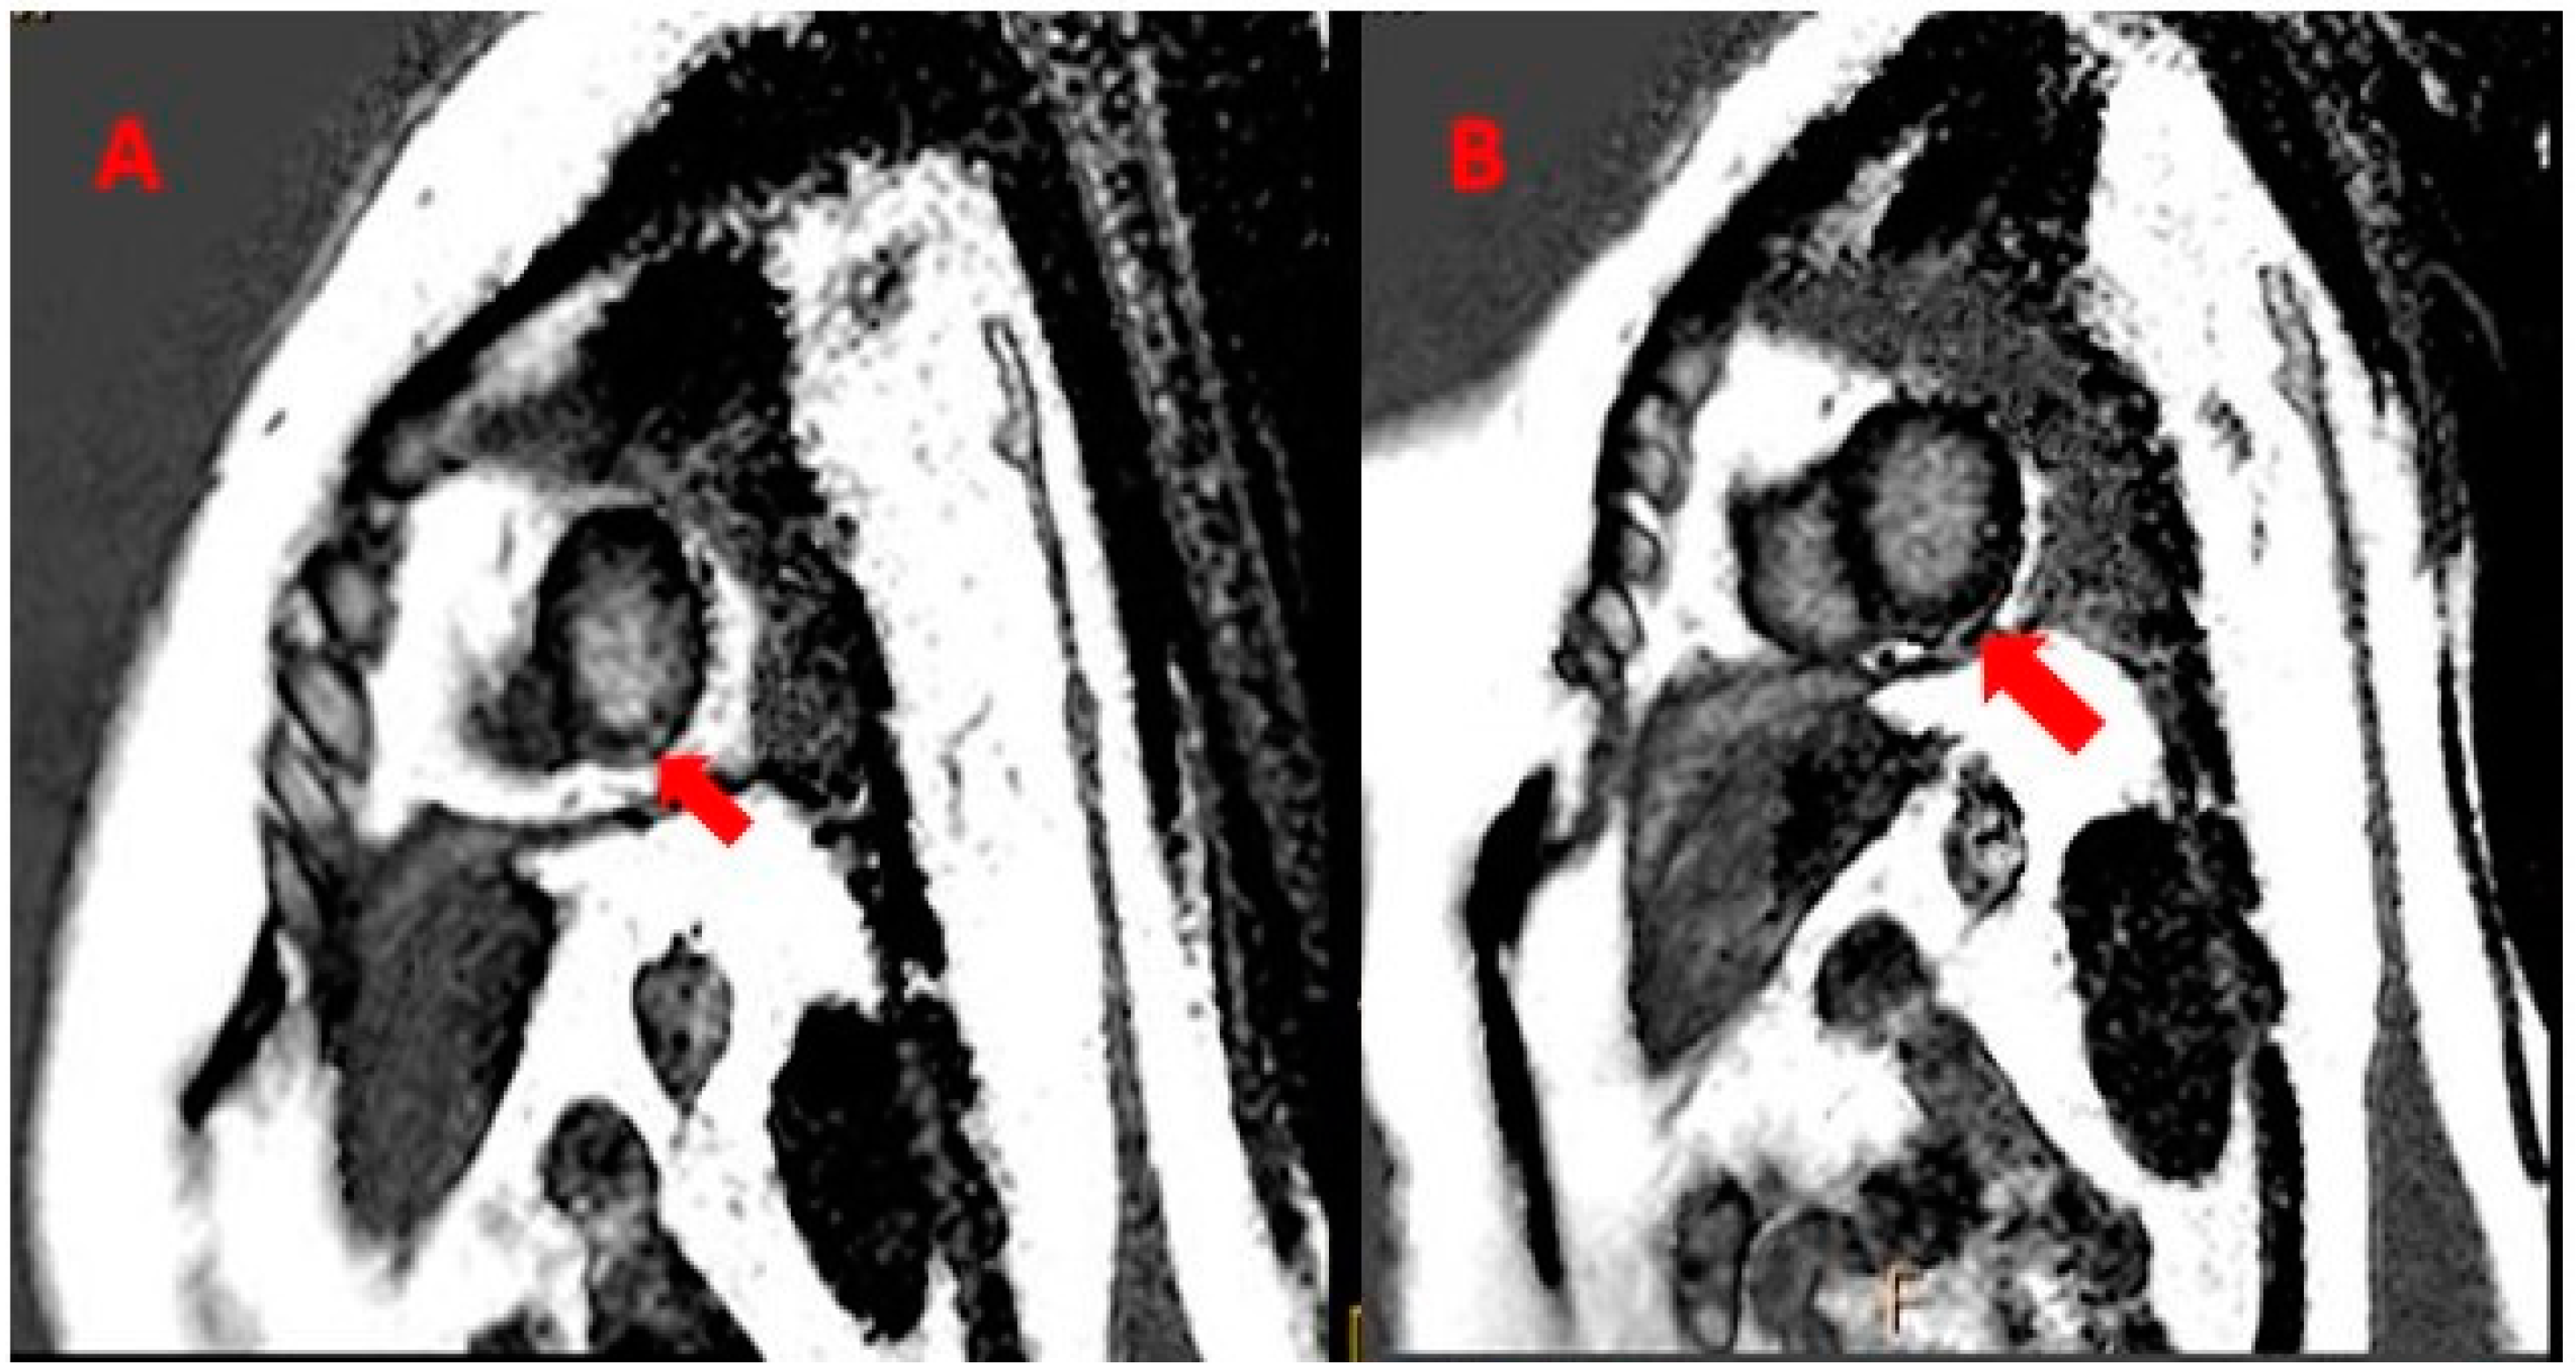

A CT scan of the spine and MRI of the heart were performed, revealing Sub-endocardial Late gadolinium Enhancement (LGE) in the inferior lateral left ventricular (Figure 3A); mild mitral regurgitation and minimal pericardial effusion were noted (Figure 3B). After consultation with a cardiologist, a diagnosis of myocarditis (stage 3) was made on clinical grounds.

Figure 3. MRI of the heart, showing LGE in inferior lateral left ventricular (red arrows) (A). In addition, minimal pericardial effusion was noted (red arrows) (B).